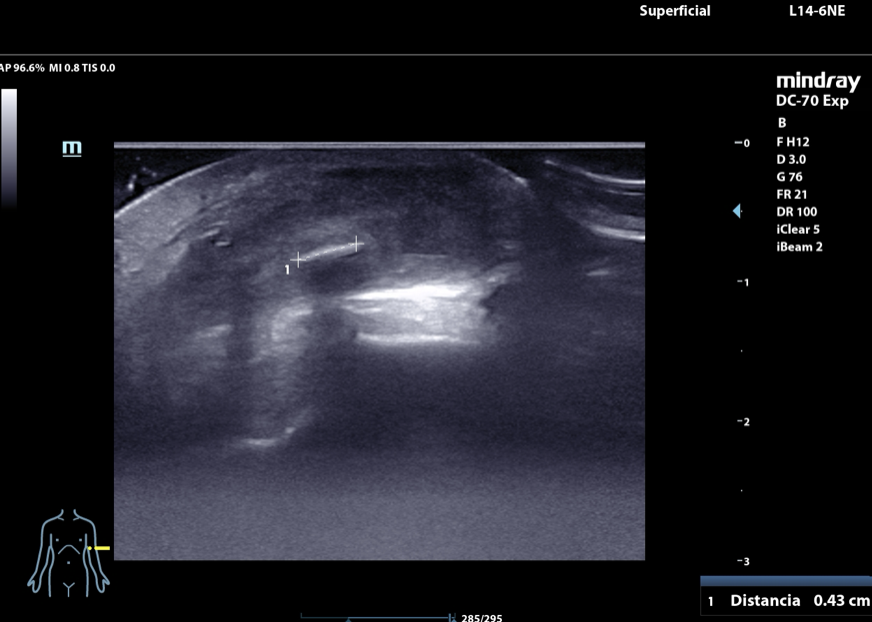

• Ecografía músculoesquelética en agosto de 2024 en la que se identifica un cuerpo extraño de 43 mm de longitud que deja sombra posterior y que se localiza a nivel del vientre del músculo braquioradial.